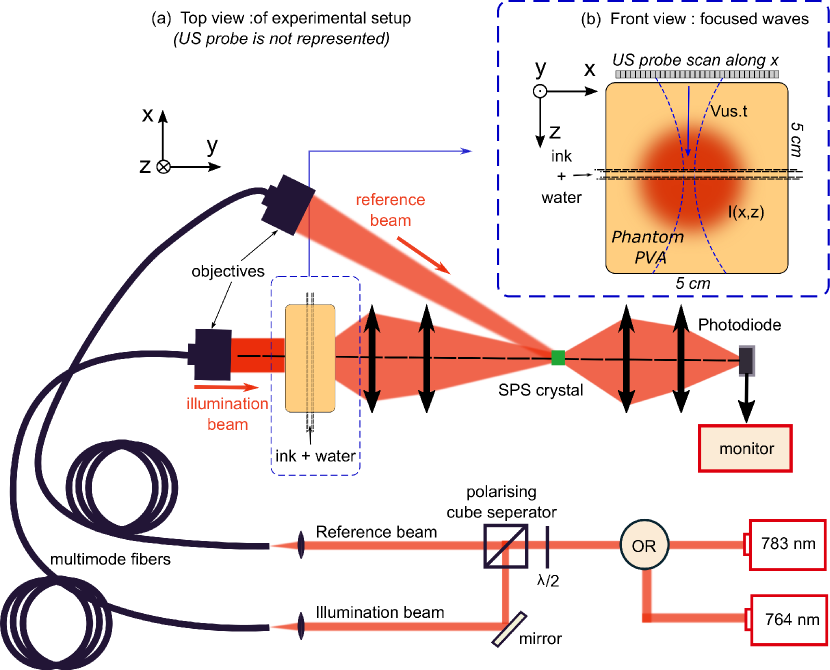

AO imaging is sensitive both to scattering and absorption. To study the influence of local variations only in absorption, a HxLxW = phantom was made out of 10% Polyvinyl alcohol phantom (PVA) with [32]. A plastic tube was inserted in the transverse direction , as shown in Fig 1(b), and filled with China ink diluted in a variable volume of water such as to vary its absorption coefficient . The full experimental setup is shown in Fig 1(a). Using a flip mirror, we illuminated the sample either with a single mode Master Oscillator Power Amplifier (MOPA, Sacher Lasertechnik GmBH) System at or with an external-cavity diode laser system developed by Norlase and DTU Fotonik at [33]. A commercial ultrasonic probe (SL10-2,0.2mm pitch from Supersonic Imaging) was used to image the tube in the plane orthogonal to the optical axis. Photons scattering through the phantom were collected by a set of two lenses and refocused on a Te-dopped photorefractive crystal (SPS:Te1%), in negative gain configuration [34, 35] where it undergone a two-wave mixing process, with a plane wave reference beam of . The back surface of the crystal was then imaged onto a photodiode (Thorlabs PDA36 A). The resulting voltage was filtered between and to keep only the AC component of the signal.